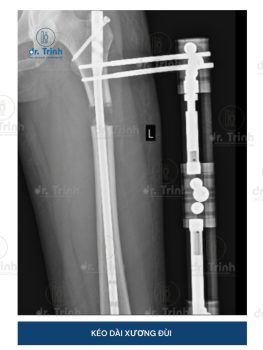

Dr.Trình Và Bước Đột Phá Trong Phẫu Thuật Kéo Dài Xương Đùi

ThS.BS Lê Khánh Trình (Dr.Trình), bác sĩ phẫu thuật đầu tiên thực hiện phẫu thuật...